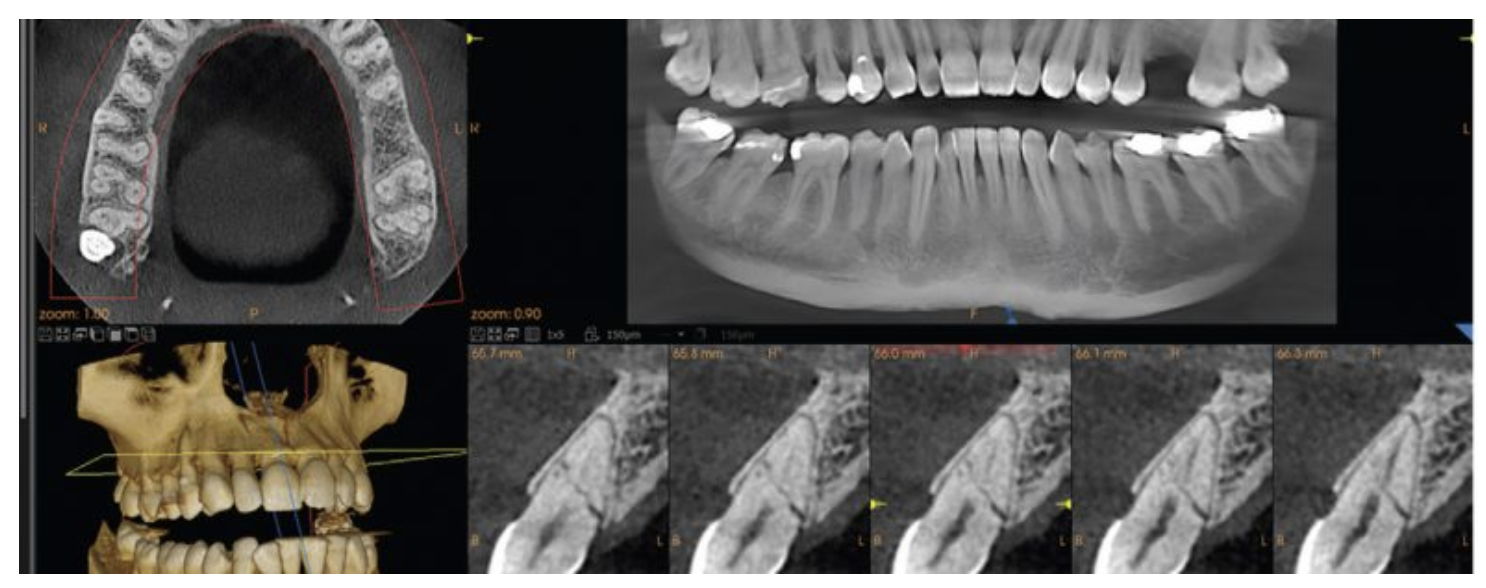

A CBCT (Cone Beam Computed Tomography) scan is a 3D dental imaging technology that captures detailed views of teeth, jawbone, nerves, and surrounding structures using a rotating cone-shaped X-ray beam.

CBCT = 3D dental imaging

X-ray = 2D flat image

The fundamental difference between CBCT and conventional X-rays lies in depth. CBCT provides a true 3D understanding of anatomy, while X-rays offer a flat 2D projection making them suitable for different clinical purposes.

| Factor | CBCT Scan | Conventional X-Ray |

| Image Type | 3D volumetric | 2D flat |

| Detail Level | High | Moderate |

| Depth Visibility | Yes | No |

| Data Output | 100–200 MB | Few MB |

| Use Case | Complex diagnosis | Routine checks |